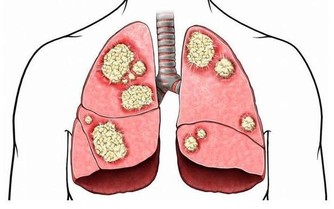

長期體內不間斷的惡性循環,久而久之就會導致致癌物在體內累積,引發各種癌症。

毒素蓄積的後果:皮膚粗糙,腹脹,腹痛,大腸癌!!

糞便留在腸道內,有害物質被再次吸收,可引起胃腸神經功能紊亂而致食欲不振、腸胃不適、腹部脹滿、口苦、肛門排氣多等表現,甚至可誘發結腸癌。

「臉色發暗」每天的呼吸都會將空氣中漂浮的細菌、病毒、粉塵等有害物質帶入肺臟。

中醫認為肺管理全身的皮膚,皮膚是否潤澤、白皙,都要靠肺的良好功能。

當肺中毒素較多時,毒素會隨著肺的作用沉積到皮膚上,使膚色看起來沒有光澤。